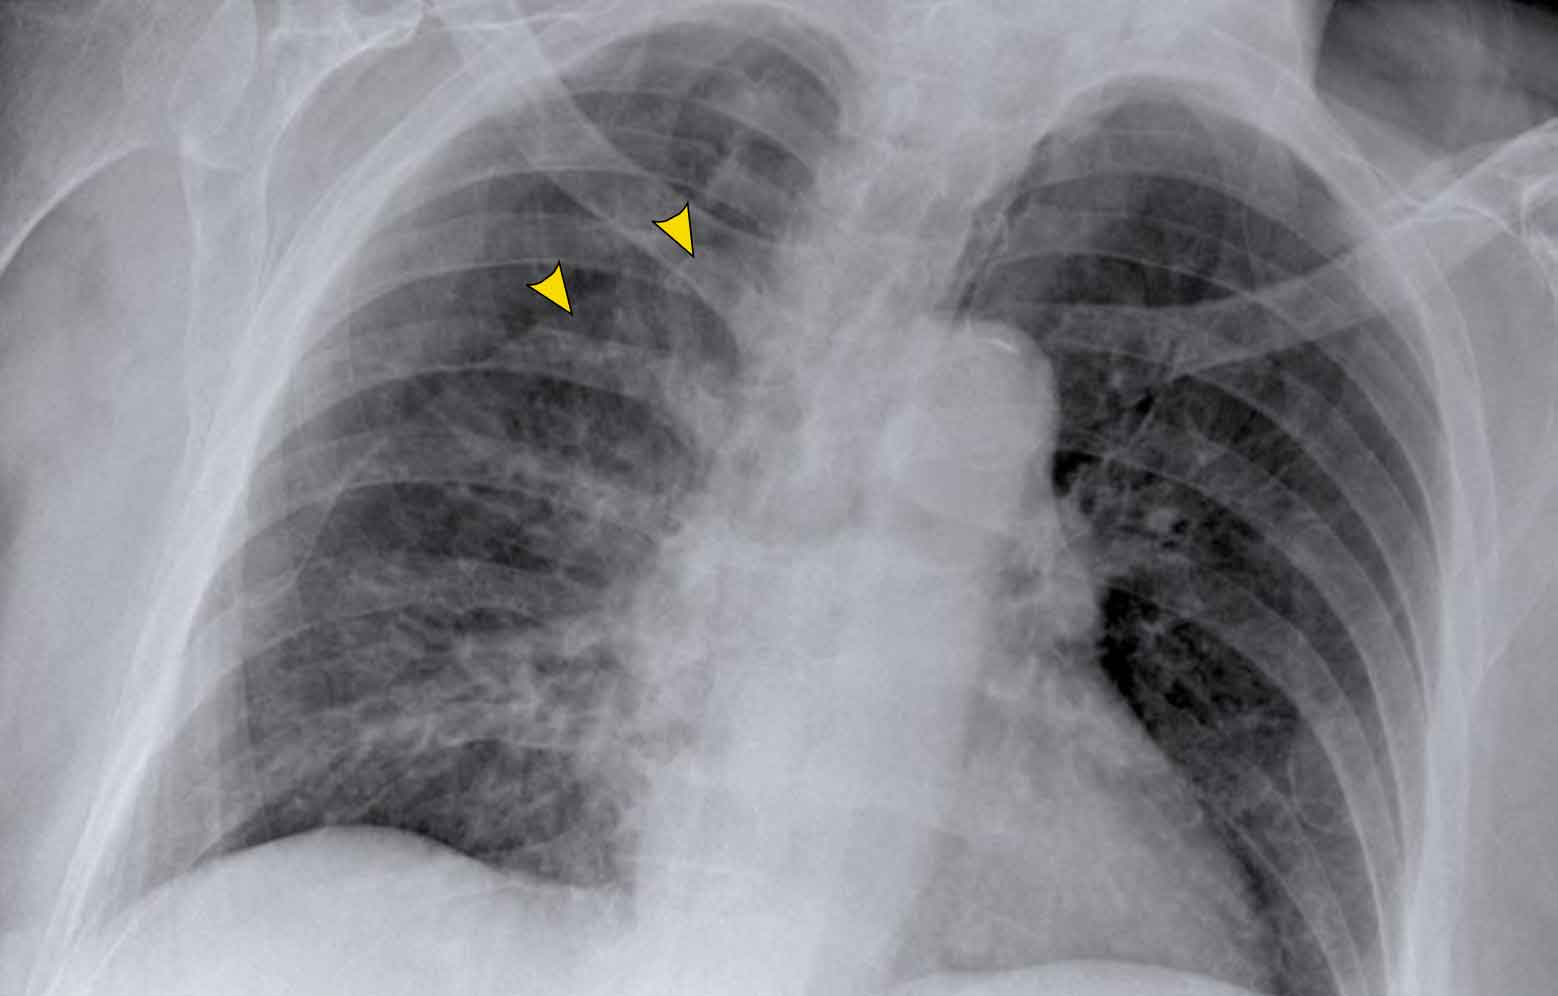

Hilar enlargement - case 1

In this case there is an enlarged hilar shadow on both sides.

This could be the result of enlarged vessels or enlarged lymph nodes.

A very helpful finding in this case is the mass on the right of the trachea.

This is known as the 1-2-3 sign in sarcoidosis, i.e. enlargement of left hilum, right hilum and paratracheal.

Here some more examples of sarcoidosis.

Click image to enlarge.

1. Lymphadenopathy and groundglass appearance of the lungs

2. Lymphadenopathy, 1-2-3 sign

3. Bulky lymphadenopathy

4. 1-2-3 sign

5. Nodular lung pattern, no lymphadenopathy

6. Hilar and paratracheal lymphadenopathy